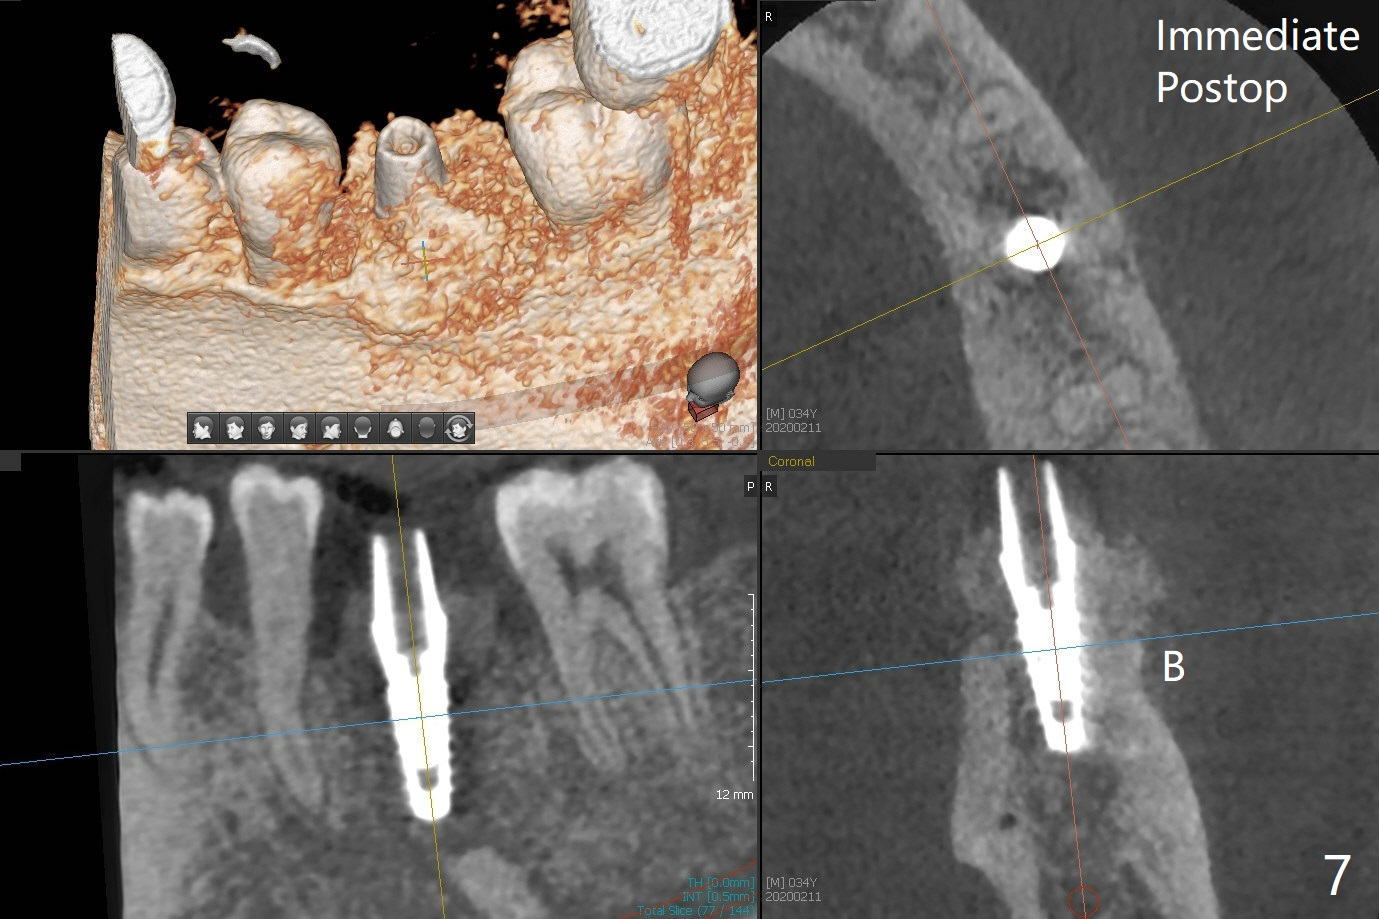

In spite of smoking reduction (1ppwk), the infection at #19, including buccal fistula (Fig.1 <) seems to be so severe that it affects pain threshold. Local anesthetics have to be added, including Bupivacaine IANB. When 4x10 mm drill is being applied, the patient feels pain. The plan is to use 4x11.5 mm drill as a final one. A 4x9 mm dummy implant is placed with 2.8 mm implant exposed (Fig.2 >), but it is subcrestal mesiodistally. Primary stability of a definitive 4.5x9 mm implant is satisfactory (Fig.3), but after initial bone graft, a 5x5.7(4) mm abutment is unable to be seated completely (<). Following 4.6 and 5.6 mm bone profile drills, the abutment remains incompletely seated (Fig.4). After fine turning, the abutment is fully seated; final round of bone graft (sticky bone) is placed mesiodistally (Fig.5 *) and buccolingually (Fig.6,7). It appears that there is tight fit between IBS implant and abutment. It is hoped that the excess bone graft with PRF is able to cover the coronal portion of the implant. If not, socket preservation should be done in this situation. In fact the implant is not placed lingual enough as compared to the design (Fig.6'). A 4.5 mm cortical drill should be used in a crown down fashion. In fact there is bone coverage coronally 5 months postop (Fig.8). Return to Prevent Molar Periimplantitis (Protocols, Table) No Deviation 12/14 Xin Wei, DDS, PhD, MS 1st edition 02/11/2020, last revision 06/30/2020